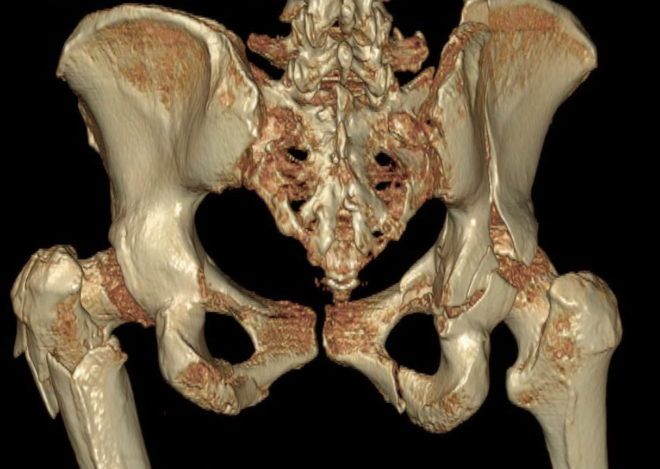

- МРТ, КТ (при надобности).

Наиболее информативным способом диагностики рассматриваемой травмы является рентгенография. Объемное изображение позволяет определить степень поражения костных элементов. Параллельно с традиционным рентгеном проводят прицельную рентгенографию, которая помогает определить, имеются ли у пациента смещения костных элементов.

Диагностические мероприятия

Как правило, после визуального осмотра пострадавшего врач проводит дополнительное обследование пальпацией, чтобы определить точное место, где произошел перелом. Прощупывание пальцами также позволяет определить, есть ли обломки костей, насколько и в какую сторону они смещены.

При диагностике очень важно для врача собрать подробный анамнез. Возможно, пациент самостоятельно не может пояснить события, которые привели к травмированию, однако могут быть свидетели, которые смогут рассказать. Ведь очень важно, было ли скручивание или сдавливание, либо человек упал. Затем обязательно проводится рентгенологическое обследование, чтобы подтвердить или опровергнуть диагноз перелома лонной кости.